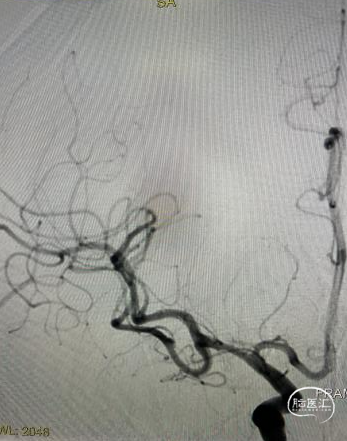

使用“零交换”技术沿21系列 Fastunnel®输送型球囊扩张导管 2.0*15mm上行自膨式闭环支架 3.0*21mm,到位后顺利释放。

清醒麻醉后,患者无新增神经定位体征,两天后顺利出院。